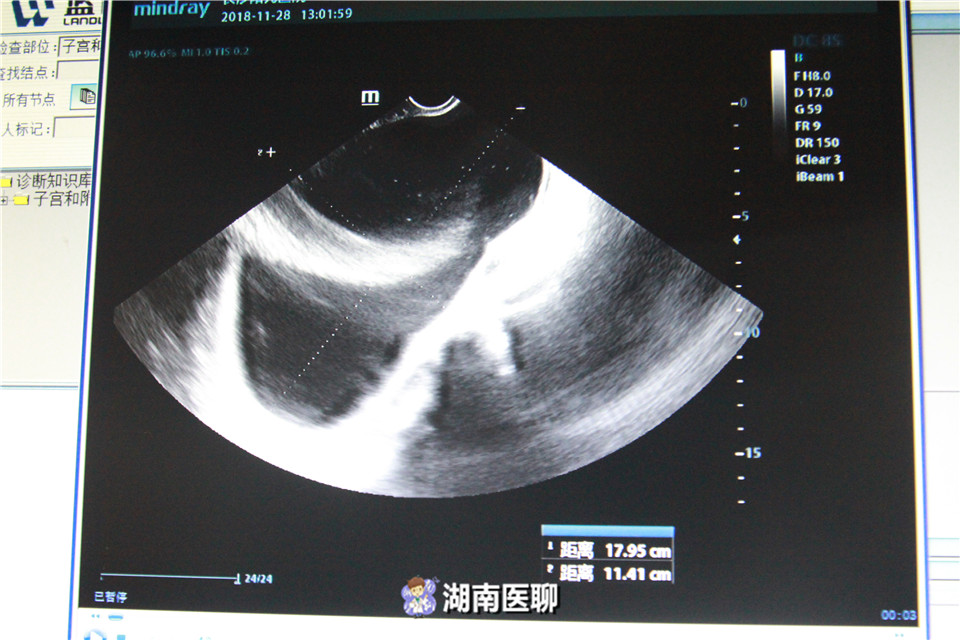

B超探查以及输卵管造影检查发现,刘女士右侧输卵管和卵巢系膜周边竟然有一个18厘米大的囊性包块,如足球般大小。